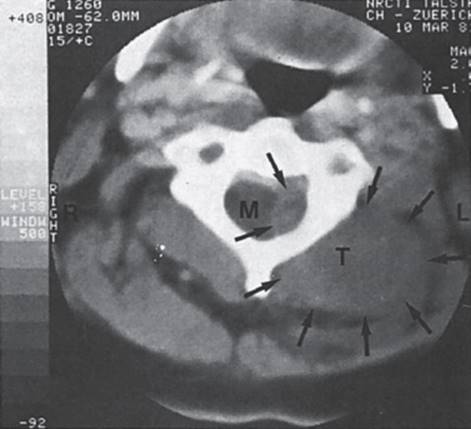

Neurinomas (also called schwannomas) are nearly as common as meningiomas and, like them, are usually found in the thoracic and abdominal regions. They arise from the Schwann cells of the spinal nerve root sheaths. They nearly always present with radicular pain and radicular deficits. A neurinoma arising from a nerve root and straddling an intervertebral foramen, so that it has both intra- and extraspinal portions, is called a dumbbell or hourglass tumor (Fig. 7.6).

Fig. 7.6 Neurinoma at C4, as seen by CT. The arrows indicate the intra and extraspinal portions of the tumor. The intraspinal portion compresses the spinal cord (c). (Image courtesy of the Neuroradiological CT Institute, PD Dr. H. Spiess, Zurich.)